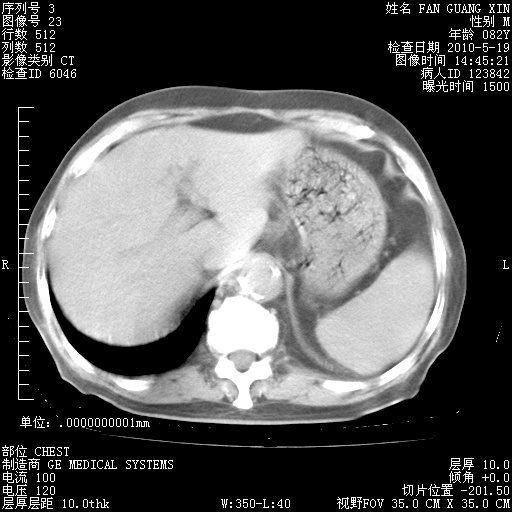

再治疗10天后的肺部CT 纵膈窗

阅读此次胸部CT,肺间质渗出性改变较入院时有吸收。目前从体温、白细胞、中性分叶明显增高,肯定存在细菌感染(发生医院感染哦,若无消化道及泌尿系统等感染的依据,肺部感染可能大)。若你院头孢哌酮舒巴坦钠耐药率较高,同意你的方案,若48小时体温仍高,可考虑使用碳青霉稀类抗菌药物,同时可予超声雾化、注意滴数时加大液体量。白蛋白33.30g/L较低哦,需加强营养等支持治疗。